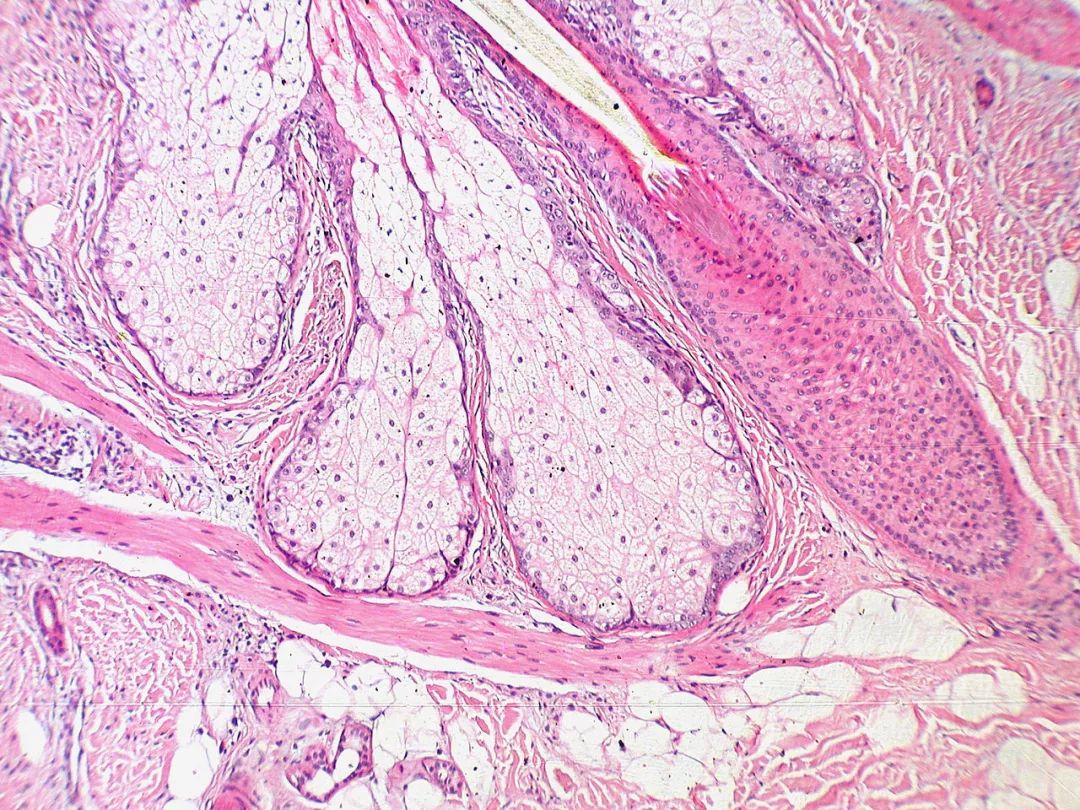

还是没印象?看看这张苏木精-伊红染色的切片,不知道会不会稍微唤起一点你的回忆。

为了观察细胞内部的结构,需要用一些东西选择性地染细胞中一部分物质的颜色。苏木精氧化后可以形成苏木因(haematein),后者可以与某些特定金属离子(主要是三价的铁离子与铝离子)结合形成有色复合物,铝-苏木因复合物呈碱性,可以将核酸染成紫蓝色;而另外一种色素——伊红呈酸性,可以将细胞浆染成粉红色。二者配合使用,便是传说中的苏木精-伊红染色(常缩写为h&e染色),可以清楚地把细胞内的各个组分区分开来,为生物学与医学的发展贡献良多。

经h&e染色的布伦内罗氏瘤切片。